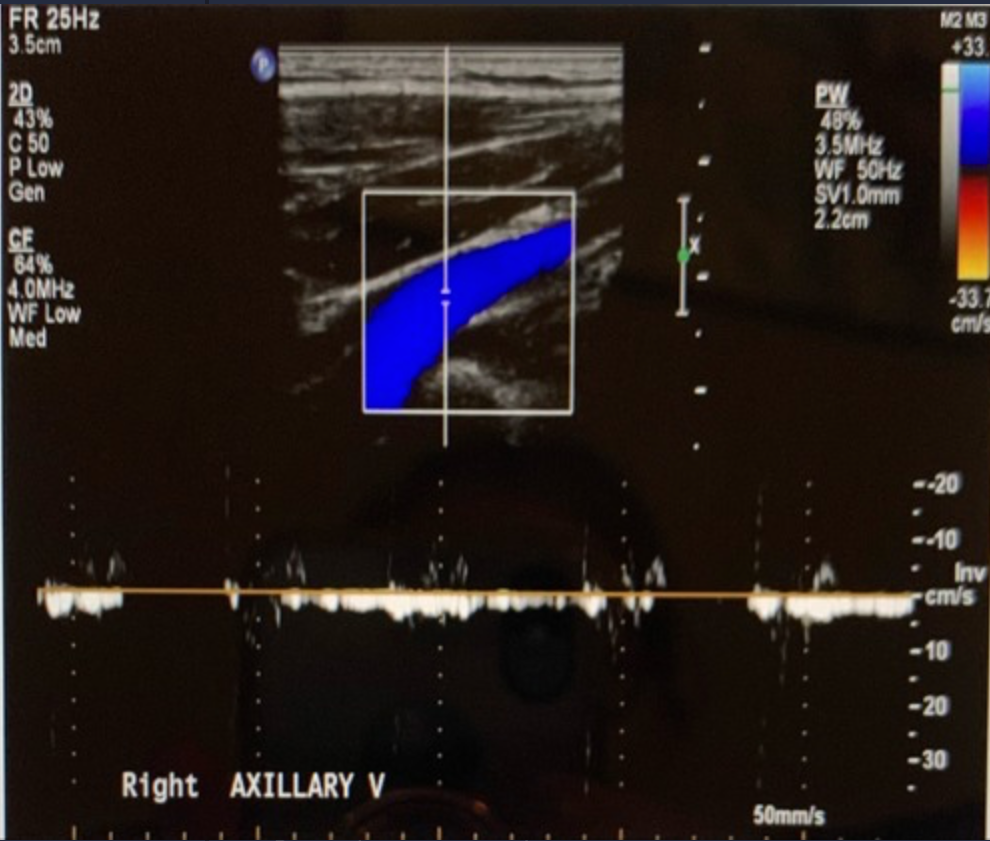

<p>What color Doppler artifact is demonstrated on the image?</p><p>a. cross talk <br>b. flash<br>c. mirror image<br>d. defocusing</p>

What color Doppler artifact is demonstrated on the image?

a. cross talk

b. flash

c. mirror image

d. defocusing

flash